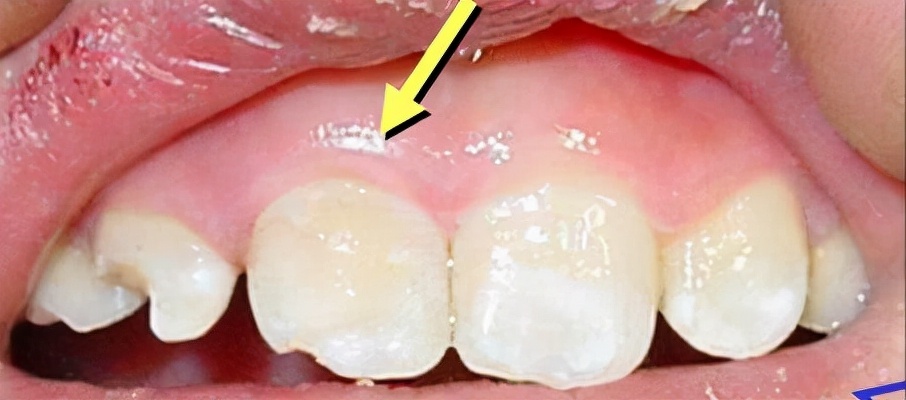

牙齿外伤分好几种情况,折断是其中一种,折断并暴露牙髓的牙齿在一定时间内是有可能“接”回去的!因为牙髓外面有一层牙周细胞膜,离开牙齿后不会马上失活,这时候我们要保证折断的牙齿没有受到二次伤害,比如干燥、过度清洁,就是不要拿纸巾去吸干水分、不要在水下面大力冲洗,更不要用肥皂、洗手液这类的东西去做清洁。

那折断的牙齿怎么保存呢?两个方法,放回嘴巴里或者泡在牛奶里,对于年龄较小的小朋友为了防止误吞,条件允许的情况下就用牛奶泡着,如果没有牛奶,就建议让小朋友把折断的牙齿压在舌头下面保存,对比直接含在嘴巴里面来说更安全一些,误吞误咽的可能性更小。

牙齿保存好了,下一步要做什么?半个小时之内找到一个靠谱的医生,有很大概率可以把断牙接回去!接回去的意思不止是说把断掉的部分像补牙那样安上,是在恢复牙齿外观的同时,“救活”这颗牙齿,而不是像根管治疗那样“杀死”牙神经,留下一颗脆弱的“死”牙齿。